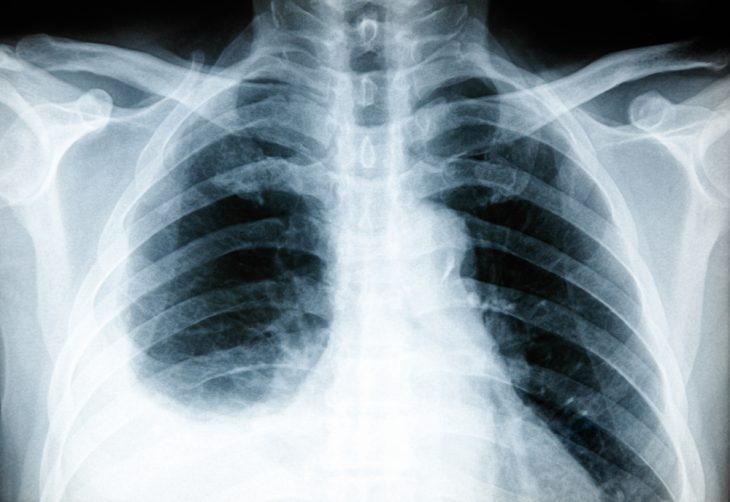

- рентгенография органов грудной клетки (высокое стояние купола диафрагмы, неровный ее контур, помутнение части легочного поля);

- рентгеноскопия легких (ограничение экскурсии диафрагмы на стороне поражения);